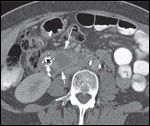

DR. PAUL RUSS: The initial CT scan of the abdomen with intravenous and oral contrast revealed a 2.7-cm, hypodense, hypovascular, solid mass in the head of the pancreas and also involving the uncinate process. In addition, there was dilatation of the pancreatic, intrahepatic and extrahepatic ducts without any evidence of distant metastatic or lymph node involvement. However, the second CT scan done, at the time of her clinic visit, showed post-surgical changes with an ill-defined soft tissue mass in the operative bed. There were also five new hypodense lesions in the liver, with the largest lesion in the anterior segment measuring 1.3 × 1.5 cm. There were two lesions in the dome, measuring 1.1 cm and 8 mm, along with two additional subcentimeter lesions in the right lobe (Figures 1A-1D, 2).

DR. PAUL RUSS: Because pancreatic adenocarcinoma is typically hypovascular compared to background pancreas and liver, the primary neoplasm is depicted as hypodense to the pancreas, and metastases as hypodense to the liver. However, some pancreatic adenocarcinomas remain occult, even with the use of advanced CT techniques, and in those cases the diagnosis can sometimes be surmised by using indirect, secondary signs like pancreatic and/or bile duct dilatation, and post-obstructive pancreatic atrophy. In this case, we see one of the typical hypodense lesions consistent with metastatic pancreatic cancer.